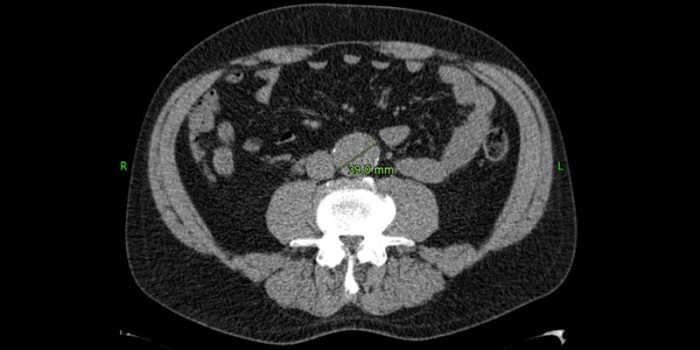

Een 49-jarige man, bekend met hypertensie en sinds enkele jaren gestopt met roken, bezocht in 2013 de spoedeisende hulp in verband met mogelijke nierstenen. Op de CT-scan van het abdomen werd, als toevalsbevinding, een ‘klein’ aneurysma van de buikaorta ontdekt met een diameter van 3,9 cm [figuur 1].

Figuur 1 | Aneurysma van de buikaorta in 2013: diameter 3,9 cm